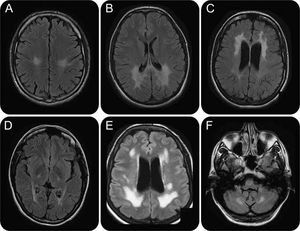

Krabbe disease, also known as globoid cell leukodystrophy or galactosylceramide lipidosis, is an autosomal-recessive sphingolipidosis caused by deficient activity of the lysosomal hydrolase galactosylceramide beta-galactosidase (GALC). GALC degrades galactosylceramide, a major component of myelin, and other terminal beta-galactose–containing sphingolipids, including psychosine (galactosylsphingosine). Increased psychosine levels are believed to lead to widespread destruction of oligodendroglia in the CNS and to subsequent demyelination.